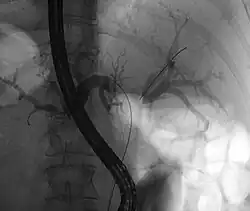

Das zuerst durchgeführte bildgebende Verfahren ist in der Regel die Ultraschalluntersuchung des Bauches. Sie eignet sich vor allem zur Erkennung gutartiger Ursachen der Symptome (wie z. B. Gallensteine) und zur Darstellung erweiterter Gallenwege bei der Cholestase. Auch Tumoren bzw. Metastasen im Lebergewebe sind im Ultraschall häufig zu erkennen. Der Klatskintumor kann unter Umständen so erkannt werden. Generell eignet sich Ultraschall aber nicht zur sicheren Darstellung des Tumors und zur Ausbreitungsbestimmung. Die Untersuchung der Wahl dafür ist die Computertomographie (CT) mit Kontrastmittel von Brustkorb und Bauch. Hier kann die Lage und Ausbreitung des Tumors bestimmt werden und dazu, ob bereits Lymphknoten befallen sind und ob der Tumor benachbarte Blutgefäße wie die Pfortader ummauert oder in sie einwächst. Zur Planung der Operation können hier auch die Lebergefäße dargestellt und die Größe der Lebersegmente und das verbleibende Lebervolumen berechnet werden. Die Untersuchung ist ein wichtiger Teil der Stadienbestimmung. Ergänzend kann eine Magnetresonanztomographie (MRT) mit Kontrastmittel zur besseren Darstellung der Gallenwege und des Tumors durchgeführt werden. Die sonst bei Erkrankungen der Gallenwege häufig eingesetzte ERCP, eine invasive Methode zur Darstellung der Gallenwege mit der Möglichkeit zur Intervention, wird bei Verdacht auf Klatskintumoren zurückhaltend eingesetzt, da hier das Risiko für eine bakterielle Cholangitis deutlich erhöht ist. Alternativ bietet sich die nicht-invasive MRCP an. Die ERCP kommt vor allem bei unklaren Fällen zum Einsatz, um mit einer kleinen Bürste Zellen aus dem verdächtigen Gangabschnitt zu gewinnen (Biopsie). Diese können bei der Diagnose den Weg weisen. Die ERCP ermöglicht auch therapeutisch die Einlage von Stents zur Entlastung der Cholestase.[3][8][13]